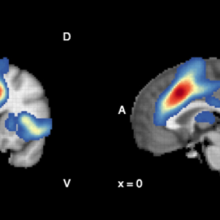

Antioxidants in the brain linked to improved treatment results in patients with psychosis

Once patients with psychosis start treatment, some get better in weeks while it can take months for others. A research team from Lawson and Western University studied antioxidant levels in the brain, and found that these chemicals, which rid the body of normal metabolic biproducts called free radicals, may improve outcomes of early intervention in psychosis. Read more.